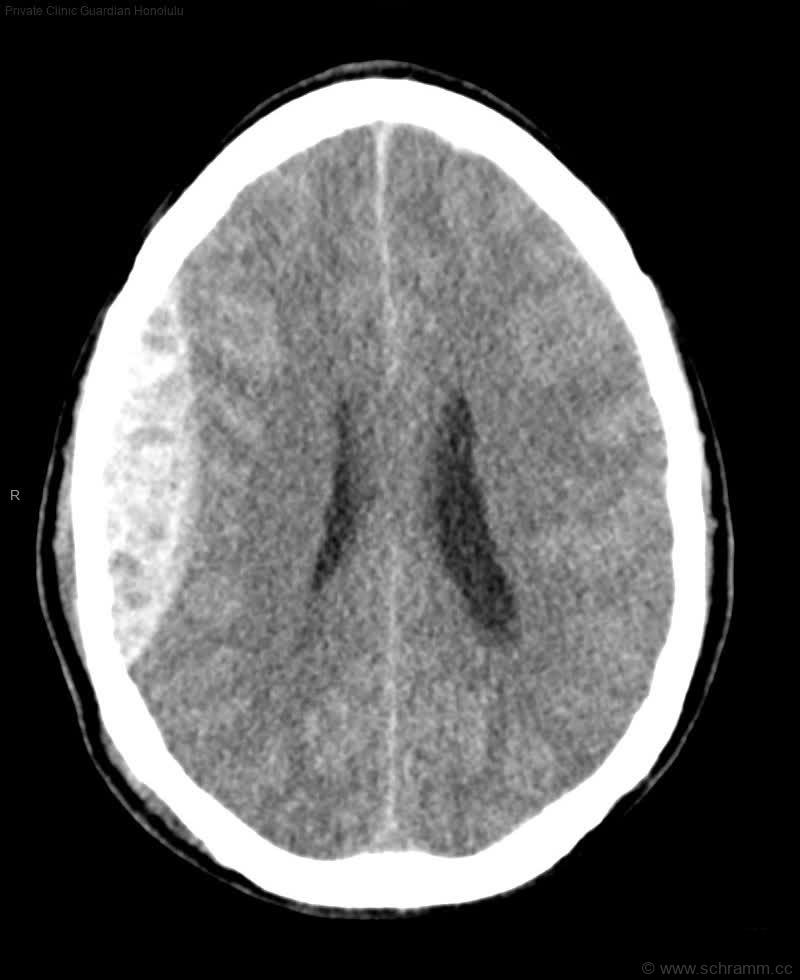

In der folgenden craniellen Computertomographie (CCT) findet sich ein(e):

Das epidurale Hämatom entsteht durch eine akute Blutung meist aus der A. meningea media zwischen Schädelknochen und Dura mater. Im diesem CCT zeigt sich eine bikonvexe, hyperdense, scharf begrenzte Raumforderung, als typischer Befund für ein epidurales Hämatom. Eine notfallmäßige neurochirurgische Eröffnung des Schädelknochens (Trepanation) ist i.d.R. bei einem epiduralen Hämatom indiziert.